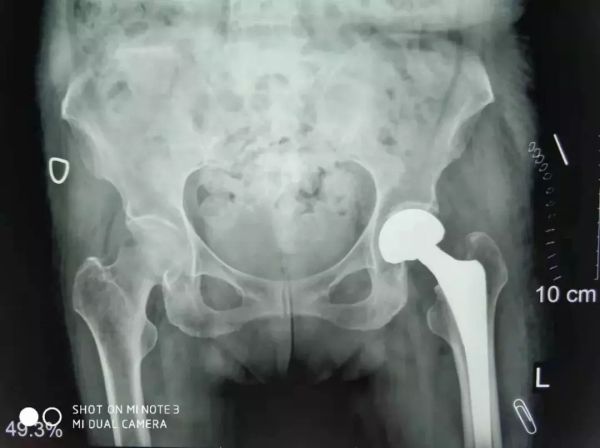

關(guān)節(jié)科羅軍主任和易觀俊主治醫(yī)師聯(lián)合麻醉科、內(nèi)科、超聲科專(zhuān)家集體會(huì)診及評(píng)估,并確定了最佳手術(shù)方式和麻醉方案,并積極做好充分的術(shù)前準(zhǔn)備。于是,11月2日在危立軍副院長(zhǎng)帶領(lǐng)手術(shù)團(tuán)隊(duì)按照術(shù)前的討論方案,在腰部麻醉下行人工股骨頭置換,手術(shù)僅用了20分鐘。

患者股骨頭置換手術(shù)照片